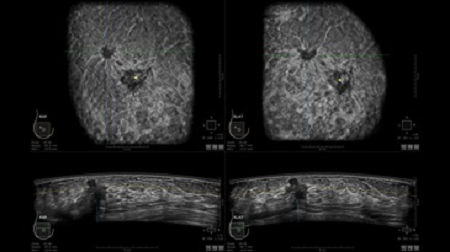

• Получение объемных 3D изображений с возможностью покадрового просмотра

• Алгоритмы обработки изображений: алгоритм однородности изображения ткани (TEA), подавление зернистости, компенсация акустической тени от соска (NSC), определение границ молочной железы (BBD), определение стенки грудной клетки

• Отображение объемных 3D ультразвуковых изображений, которые состоят из традиционных поперечных и воссозданных коронарных и сагиттальных проекций

• Стандартизованная ориентация изображения: «толстый срез» в коронарной плоскости; поперечная; сагиттальная плоскость; радиальный и антирадиальный поворот изображения; просмотр исключительно области интереса

• 360 ° APC - отображение области по «любой точке компаса»

• Одновременный просмотр двух изображений для сопоставления в коронарной плоскости